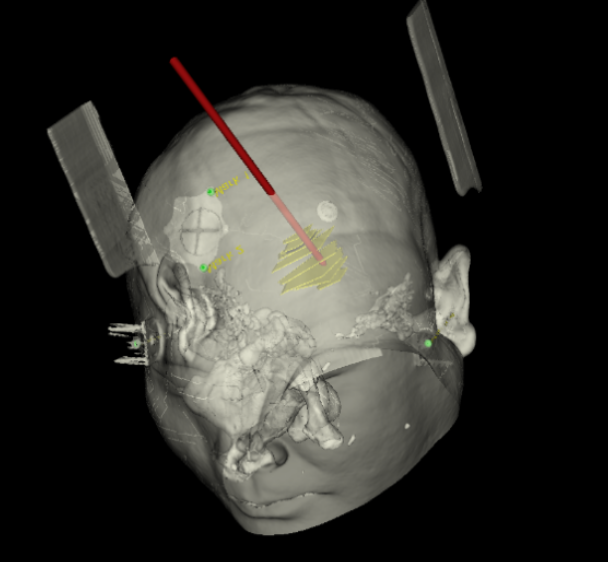

手術(shù)日當(dāng)天,醫(yī)生團(tuán)隊通過手術(shù)計劃系統(tǒng)為患者制定手術(shù)靶點及最安全的入顱路徑,隨后將手術(shù)規(guī)劃導(dǎo)入手術(shù)室的機(jī)器人當(dāng)中。

術(shù)前團(tuán)隊討論手術(shù)規(guī)劃

實際手術(shù)時,機(jī)器人在幾分鐘內(nèi)就完成了空間注冊,機(jī)械臂在定位儀的引導(dǎo)下自動定位,準(zhǔn)確鎖定靶點。

術(shù)前韓帥醫(yī)生使用“睿米”制定手術(shù)規(guī)劃

手術(shù)規(guī)劃在機(jī)器人軟件上制定完成